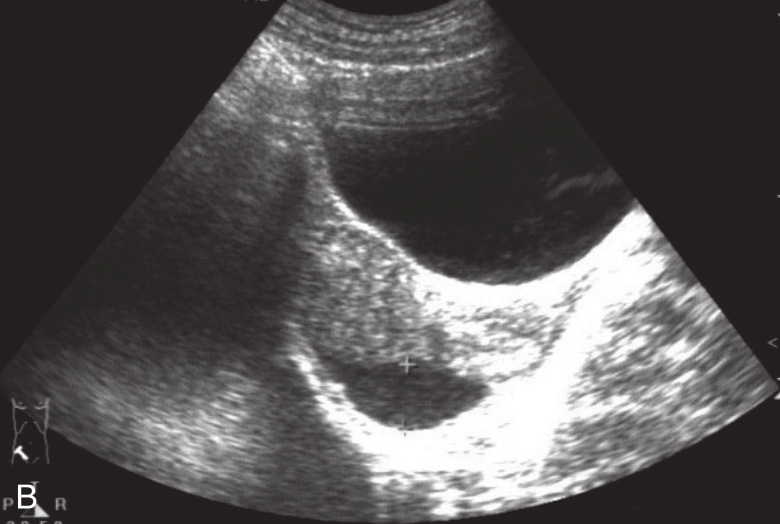

图1-12-2 真性肝破裂灰阶超声图像

A.肝右叶片状低回声区,其内血流信号不明显;B.盆腔少量积液